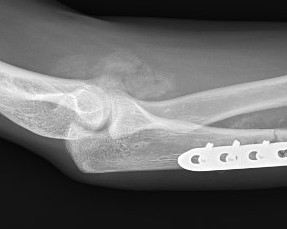

Xray

Radio-ulna synostosis

Surgical management of heterotopic ossification

Technique

Depends on site of ectopic bone